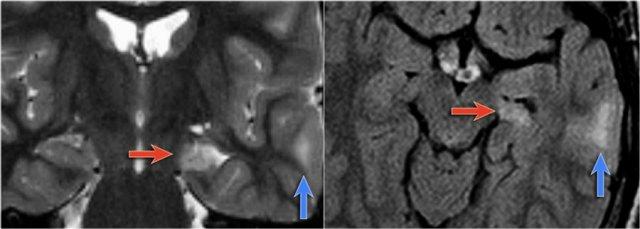

Hình ảnh T2W và FLAIR mặt phẳng coronal cho thấy xơ cứng thùy thái dương trong bên phải.

Lưu ý tình trạng mất thể tích, biểu hiện của teo não, gây giãn thứ phát sừng thái dương của não thất bên.

Tín hiệu cao trong hải mã phản ánh tình trạng gliosis.

Hình ảnh cho thấy xơ cứng thùy thái dương trong với hải mã tăng tín hiệu và teo nhỏ (mũi tên đỏ), kèm theo giãn thứ phát sừng thái dương trái của não thất bên trái.

Cũng cần lưu ý tình trạng tăng tín hiệu dưới vỏ não kết hợp ở thùy thái dương trái, gợi ý loạn sản vỏ não khu trú.